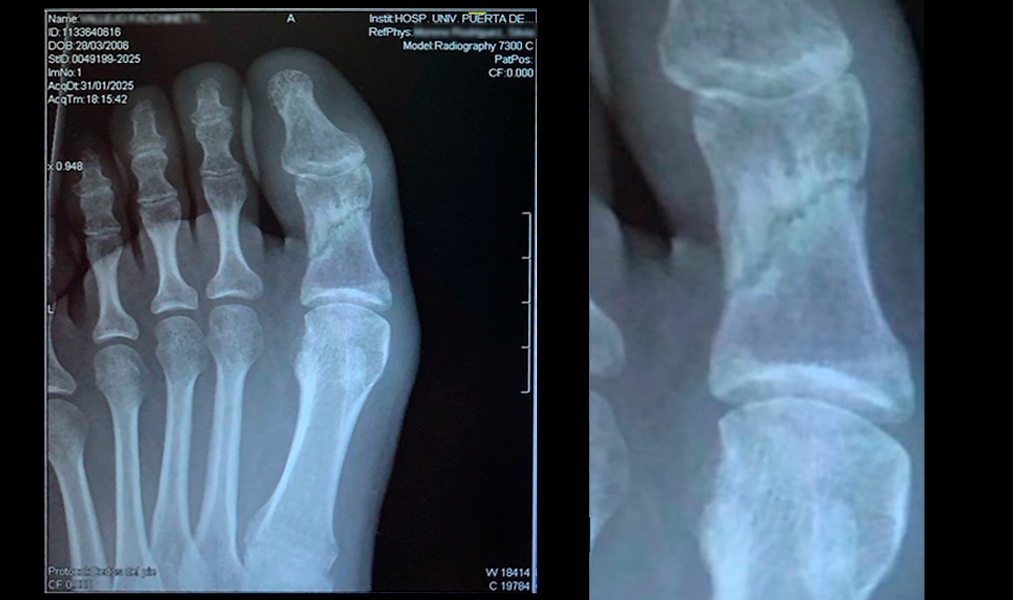

Datos del paciente

Paciente de 19 años

Motivo de la consulta

El paciente acude a la consulta con una fractura de la falange proximal del primer dedo. Después de 4 meses no le consolidaba la fractura.

Diagnóstico

- Fractura de la falange proximal del primer dedo

- Se observa en imagen perfectamente